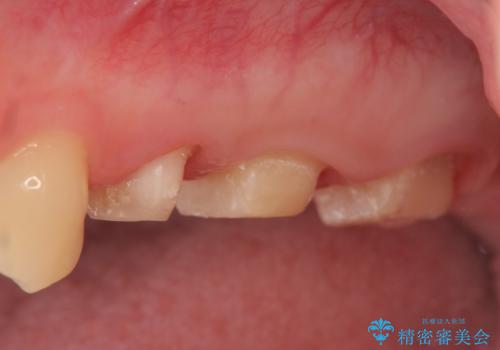

- 左上の歯が痛くてものが咬めないといらっしゃった方の症例です。

左上6は自発痛および持続痛を認めたため根管治療後、オールセラミッククラウンによる補綴を行いました。

左上7は冷水痛のみだったため、慎重に虫歯の除去を行い症状がないことを確認後、オールセラミッククラウンによる補綴を行いました。

左上5は再根管治療後、オールセラミッククラウンによる補綴を行いました。